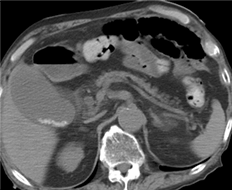

CT、MRIで膵管狭窄はある

が腫瘤は指摘できず

超音波内視鏡のみで

膵管狭窄部に膵腫瘤を指摘